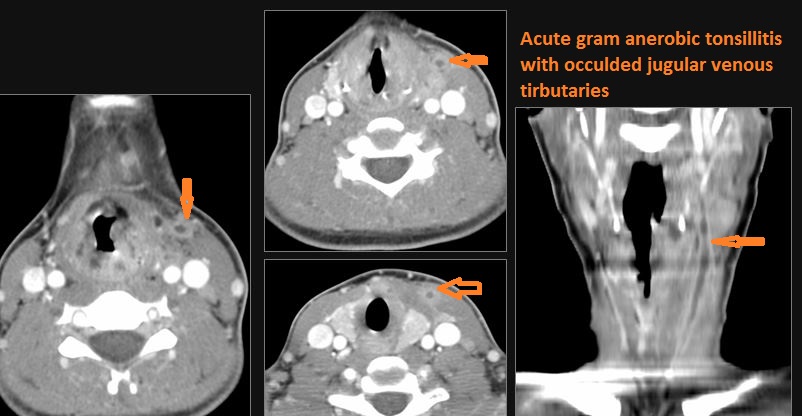

There is excessive enhancement or thickening of the mucosa or hypertrophy of the palatine or lingual tonsillar tissue or the lymphoid tissue along the glossotonsillar sulci and posterior pharyngeal wall.

There is abscess at the periphery of the lymphoid tissue of the palatine tonsil within the potential peritonsillar space.

Vascular Findings